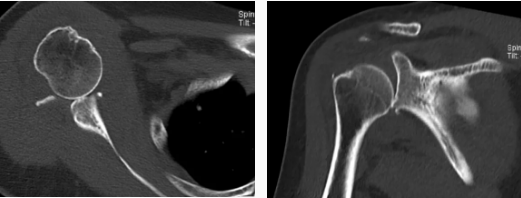

病例2

病史摘要:女性,65歲,跌傷致右肩活動(dòng)受限9天。

CT圖示:右側(cè)肱骨頭后上部局部明顯凹陷,局部骨皮質(zhì)欠光整(箭頭),外緣見(jiàn)小片狀骨碎片影;右側(cè)肱骨頭向下方移位,關(guān)節(jié)間隙增寬;前下盂唇骨質(zhì)不連續(xù),見(jiàn)多發(fā)小碎骨片影并游離(三角形)。

MR圖示:右側(cè)肱骨頭后上部局部明顯凹陷,骨皮質(zhì)欠光整,周圍見(jiàn)片狀壓脂高信號(hào)影(箭頭);前盂唇脫離移位;前下盂唇不連,局部骨質(zhì)分離(三角形);肱骨頭向前移位。